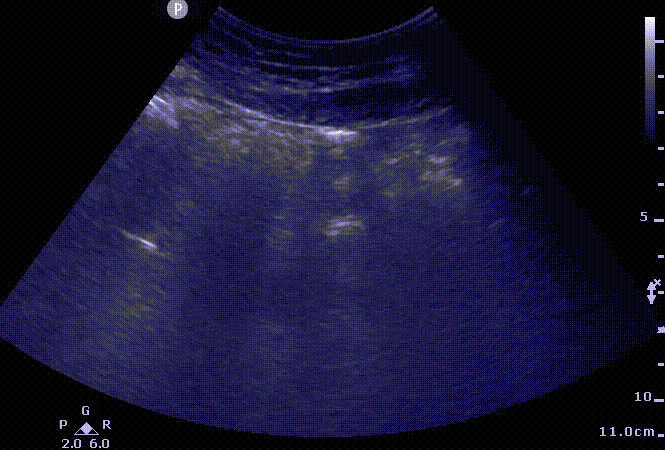

Sonographic view of ascites. Simple ascites visualized. Anechoic fluid is visualized with this curved-linear probe and most likely corresponds to transudate. Notice the acoustic enhancement created by the presence of fluid in the abdomen. The ascites safety zone (line in blue) on this clip corresponds to approximately 3 cm. So the needle will have to penetrate the muscular wall (in purple) and then have the safety zone before injuring bowel wall in this location.

The needle insertion site should be evaluated in multiple planes to ensure avoidance of underlying abdominal organs and detect blood vessels along the planned needle trajectory. Color Flow Doppler should be used to assess for superficial vessels along the anticipated needle trajectory (not shown on the clips below).

Sonographic view of ascites. This view is orthogonal (90 degrees) from the above clip. Anechoic fluid is visualized with this curved-linear probe and most likely corresponds to transudate. Notice the acoustic enhancement created by the presence of fluid in the abdomen. The safety margin looks higher on this one (blue line) compared to the prior clip. Since the bowel is closer on the prior clip we would be using that measurement instead of this one.